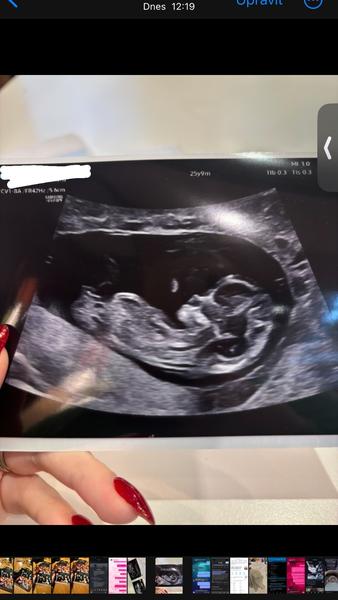

Zdravím všechny, zkouším jestli se tu na téhle diskuzi někdo třeba ještě ozve. 😅 včera jsem byla na prvním screeningu, mám u nej tuhle fotku. V návalu informaci jsem se doktorky ani nezeptala jestli už je něco třeba náznakem vidět. Je mi jasné, ze tady mi to nikdo “nevyvěští” spis mě jen zajímá jestli na fotce je vůbec vidět pohlavní hrbolek. Ja jsem v tomhle poměrně zmatená 😅

@zzuzzanna123 ano, dá se zjistit tak na 85% podle fotky ultrazvuku kolem toho 12. týdnu, ale musí tam být vidět pohlavní hrbolek, což u té tvojí fotky nevidím. Snad příště 🙂

@zzuzzanna123 musel by jit videt pohlavni hrbolek … a tohle je moc brzy, plus neni mimi tak natocene. Nejlepe se to pozna na 1.screeningu

Z tehle fotky určitě ne. Kolikaty jsi tt? To vypadá strašně mladě takovou fotku mám někdy z 10tt a to se nepozná nic :D